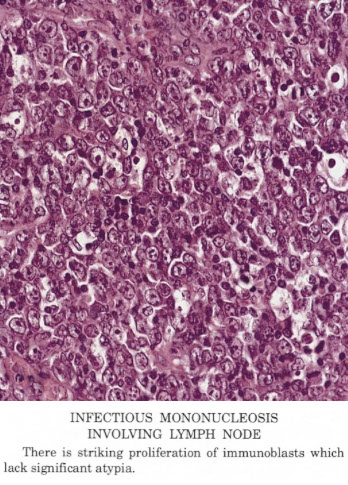

Infectious mono can look like DLBCL

Infectious Mononucleosis (IM)

Paracortical hyperplasia, paracortex with moth-eaten appearance and has lots of lymphs which can be small to large sized, as well as immunoblasts, histiocytes and plasma cells

Immunoblast phenotype: CD20+ B-cells co-expressing CD30 and MUM1, negative for CD15, EBV-EBER positive (predominantly in interfollicular areas, 10-70% of cells, median 30%) [3]

Infectious mononucleosis. Admixed population of cells of varying sizes. In areas where immunoblasts predominated (right) which could be a florid expansions, like large aggregates or sheets of cells with mitotic activity. Spend some time on low power to appreciate the normal architecture, try to find areas with a variety of cell types. Immunoblasts may resemble Reed-Sternberg (RS) cells (inset). [3]